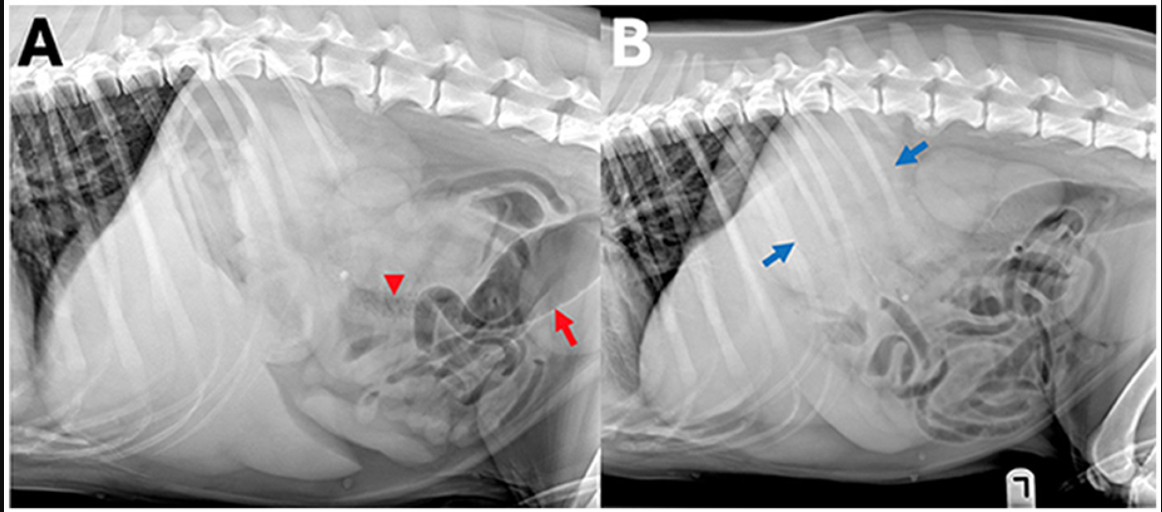

Machine learning analysis of intestinal disorders in cats

VRU 2023 64(5): 890-903